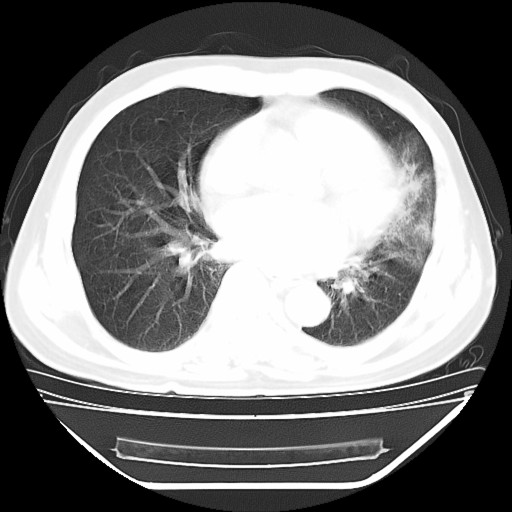

以下是引用hhcckk在2009-5-29 10:34:00的发言:[br]左下肺片絮状边缘模糊影,考虑感染,建议治疗后复查[br]